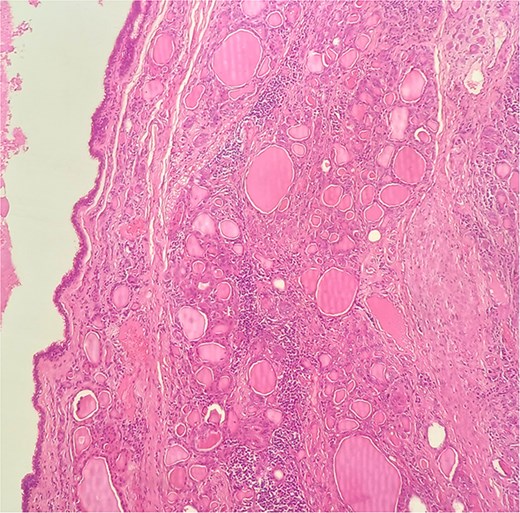

A 47-year-old woman with unremarkable medical history, presented with a 2 months history of neck mass along the midline. Physical examination revealed a 6 cm mobile, thyroid nodule without compressive symptoms. There was no associated erythema, fluctuance, tenderness or adhesion to adjacent structures. There was also no associated cervical lymphadenopathy. The rest of the physical exam was unremarkable. Laboratory tests including TSH, FT3, and FT4 revealed normal levels. On cervical ultrasound, there were a 62 mm left toto-lobar nodule classified as EU-TIRADS3, and an 11 mm right nodule, also classified as EU-TIRADS3. Fine-needle aspiration cytology concluded to a benign lesion classified as BETHESDA II. The patient reported respiratory discomfort in the supine position, leading to the indication for a lobectomy. Gross examination of the specimen revealed a toto-lobular nodule with a colloid appearance. It was well-circumscribed by a thin and regular fibrous capsule. The nodule measured 4 × 6 cm and exhibited areas of fibrous, whitish remodeling, as well as hemorrhagic and cystic changes. On microscopic examination, the nodule corresponded to a macro vesicular adenoma altered by fibrosis and hemorrhage. It was surrounded by a thin, regular, and intact fibrous capsule. However, at the periphery of the nodule, adjacent to the thyroid pseudo capsule, a 1.2 cm cystic ductal structure was observed. It showed pseudostratified ciliated columnar and squamous epithelial lining associated with thyroid follicles in the surrounding stroma (Figs 1 and 2). These thyroid follicles were bland with no papillary nuclear atypia or invasion (Fig. 3). The cyst was filled with a thin eosinophilic material (Fig. 4) Lymphocytic thyroiditis of mild severity was identified in the rest of the thyroid tissue. Based on these findings, the diagnosis of macro vesicular thyroid adenoma with ITTGDC and lymphocytic thyroiditis was made. After the surgery, the patient developed temporary dysphonia.

HE × 4 incidental finding of cystic duct structure in the adjacent thyroid gland tissue.